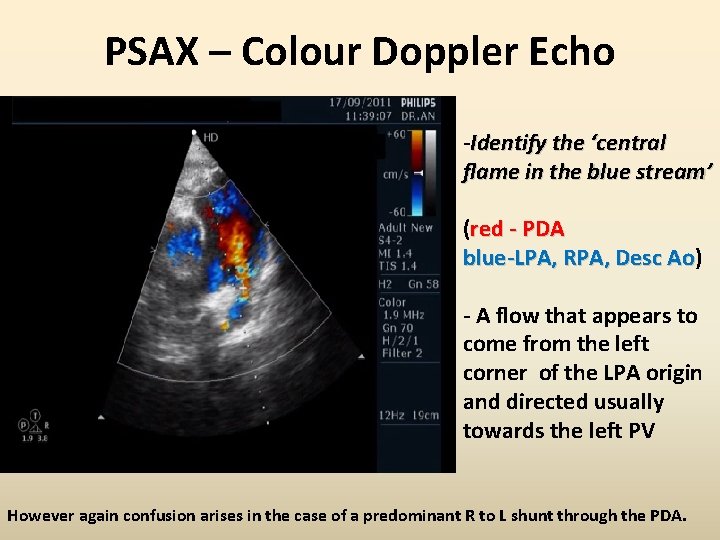

PSAX – Colour Doppler Echo -Identify the ‘central flame in the blue stream’ (red - PDA blue-LPA, RPA, Desc Ao) Ao - A flow that appears to come from the left corner of the LPA origin and directed usually towards the left PV However again confusion arises in the case of a predominant R to L shunt through the PDA.